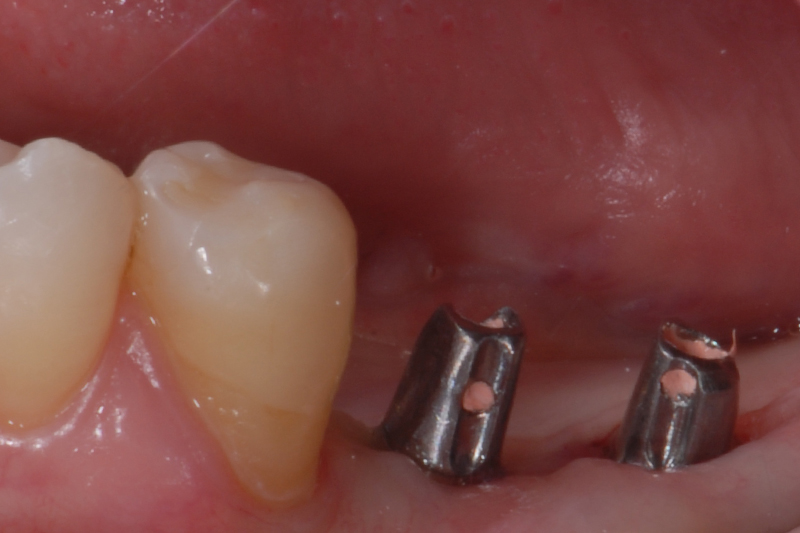

- Status kliniczny przed fazą protetyczną

- filary protetyczne w postaci łączników wprowadzone do implantów